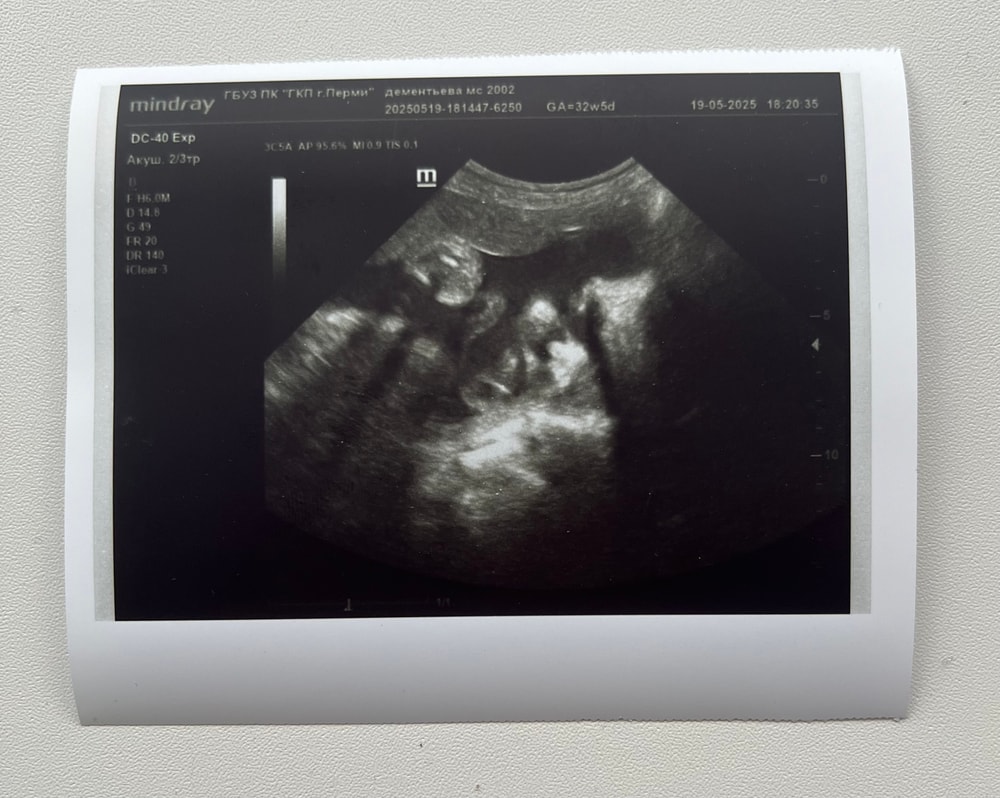

Срок 32.5 🤍 по размерам соответствует на 32.5 🙏🏼

вес 1997гр 🐣 наша девочка, наша малышечка 🥰

врач сказала, что здоровая, но маловесная, но для ер с моими параметрами говорит идеально, ещё успеем до родов набрать🤍

кровотоки в норме, обвитий нет🙏🏼 шейка матки 31мм, зев закрыт, канал сомкнут ✔️